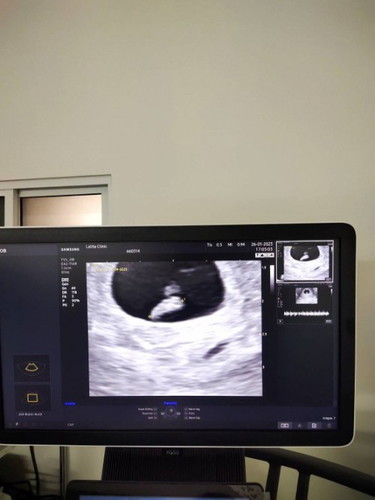

ซาวด์รอบแรกไม่เจอแม้แต่ถุงตั้งครรภ์ เครียดมาก คิดไปต่างๆนาๆ ผ่านไป 2 อาทิตย์ ตัดสินใจไปซาวด์อีกรอบ ซาวด์หน้าท้องเจอแต่ถุงตั้งครรภ์ เลยซาวด์ทางช่องคลอด ทีนี้เจอทั้งตัวและเสียงหัวใจเลย ดีใจมากๆ โล่งเลยจริงๆ 🥰 อายุครรภ์ 6w2d 🎉